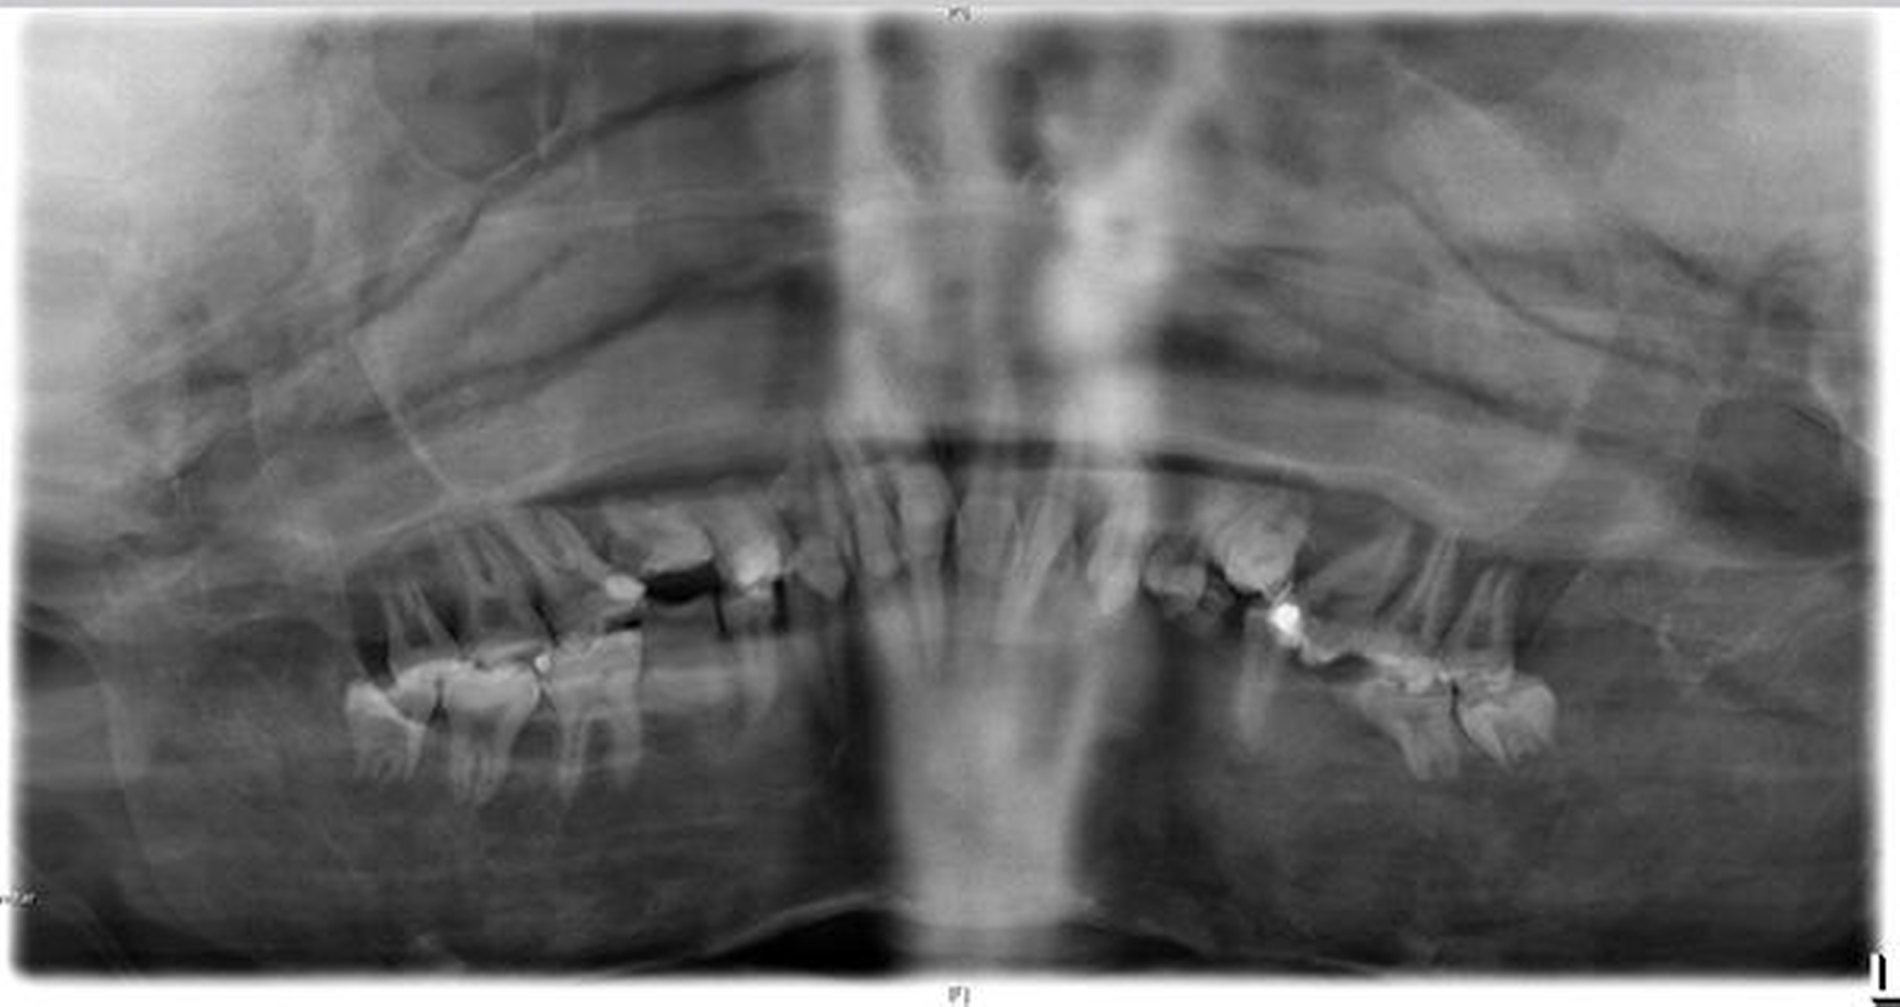

Eine Langzeitsauerstofftherapie über eine Nasenbrille war erforderlich, aufgrund der fibrösen Dysplasie wurde die Patientin seit Jahren mit Bisphosphonaten (Aredia-Infusionstherapie) behandelt. In der Panoramaschichtaufnahme zeigte sich das charakteristische Erscheinungsbild einer fibrösen Dysplasie (Abbildung 3).

Die fibröse Dysplasie tritt als klassisches Symptom beim McCune-Albright-Syndrom auf. Im Bereich des Schädelknochens ist der Alveolarfortsatz am häufigsten betroffen und führt zu einer schmerzlosen Auftreibung, die sich auf das Os zygomaticum ausbreiten und in der Folge zu Deformierungen des Gesichtsschädels führen kann [Wójcik S et al., 2016], wie dies auch im hier beschriebenen Fall vorlag.